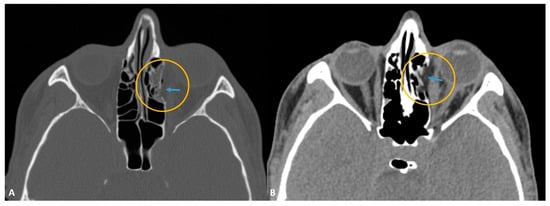

- Betts, A.M.; O’brien, W.T.; Davies, B.W.; Youssef, O.H. A systematic approach to CT evaluation of orbital trauma. Emerg. Radiol. 2014, 21, 511–531. [Google Scholar] [CrossRef] [PubMed]

- Lee, H.-J.; Jilani, M.; Frohman, L.; Baker, S. CT of orbital trauma. Emerg. Radiol. 2004, 10, 168–1672. [Google Scholar] [CrossRef] [PubMed]